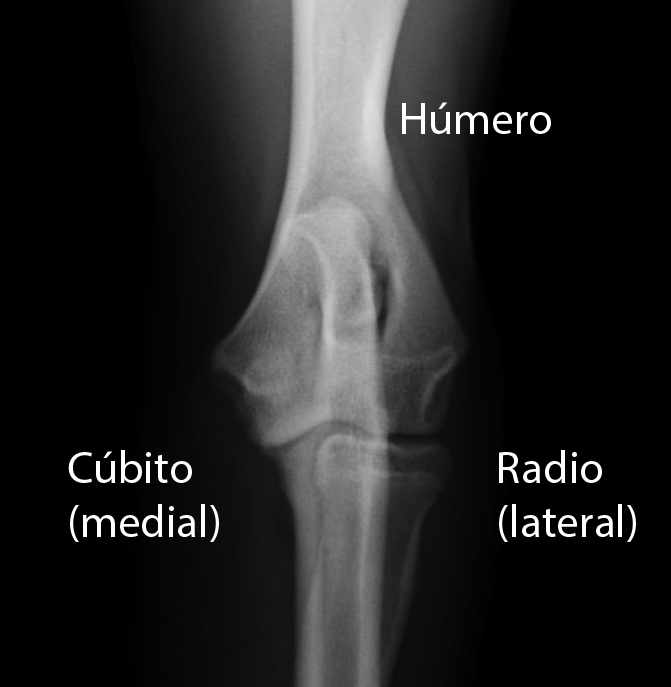

Conceptos clave. Las fracturas del húmero distal generalmente son el resultado de una caída sobre un brazo extendido o una fuerza directa; que pueden estar asociados con la lesión neurovascular. (Véase también Generalidades sobre las fracturas ). Las fracturas de húmero distal son comunes en los niños de entre 3 y 11 años.. Las fracturas proximales del húmero son proximales al cuello quirúrgico (véase figura Referencias anatómicas clave en el húmero proximal ). La mayoría están mínimamente desplazadas y anguladas. El diagnóstico es por radiografía simple o, a veces TC. La mayor parte de estas fracturas se pueden tratar con un cabestrillo, una venda, y la.

Las fracturas del extremo distal del húmero (o fracturas de la paleta humeral) representan una parte importante de la actividad traumatológica pediátrica. Casi siempre están causadas por una caída con recepción sobre la mano. La fractura supracondílea es la más frecuente con gran diferencia (dos tercios de los casos).. Las fracturas de húmero proximal son patologías que requieren una evaluación integral del paciente y las características específicas de cada individuo. El objetivo final es restaurar la función articular y evitar complicaciones secundarias al traumatismo en sí o al tratamiento quirúrgico o inmovilización.